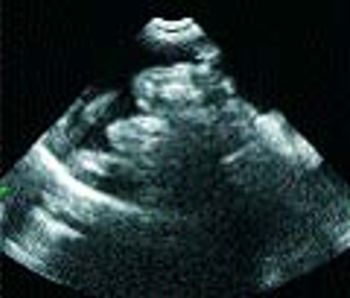

Q. Could you provide a brief review of car Could you provide a brief review of cardiomyopathies in cats?

Q. Could you provide a brief review of mitral valve insufficiency in older dogs?